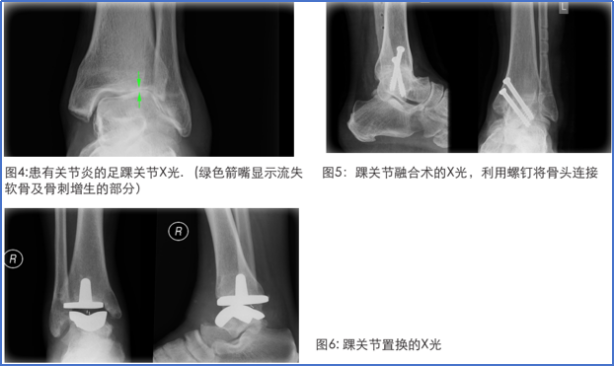

踝关节外侧扭伤后“再损伤率”和“慢性踝关节外侧不稳”发生率较高,长期来看,这两类情况会进一步引发“创伤后踝关节炎”(PTAO),同时导致患者体力活动水平下降及健康相关生活质量降低;手术治疗方法包括踝关节融合及踝关节置换等。但无论何种手术方法治疗终末期创伤性关节炎,都无法完全恢复踝关节正常功能。

图16 踝关节不稳是导致踝关节关节炎的其中一个主因(4)。患者最终或需要进行踝关节融合术(固定关节使其失去活动能力以消除关节因活动做成的痛楚)(5)或踝关节置换术(使用人工关节)(6)。